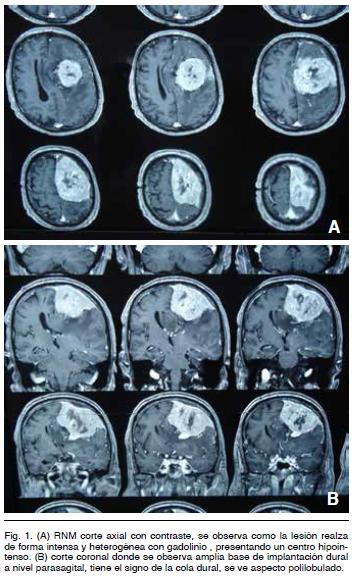

La misma evidenció (Figura 1) un tumor intracraneano extra-axial de la convexidad frontoparietal izquierda, isointenso en la secuencia T1, voluminoso, polilobulado y con extenso contacto dural que llega hasta el seno longitudinal superior y la hoz cerebral. Con la administración de gadolinio hay un realce intenso y heterogéneo del tumor y su base de implantación (signo de la cola dural).

En T2 se observa isointenso, identificándose liquido cefalorraquídeo entre el tumor y el cerebro (signo de la hendidura). Se ve también importante edema perilesional digitiforme (Figura 2).

Con respecto a los estudios de imagen, es de elección la IRM de cráneo. Como ya se mencionó, estos tumores son imagenologicamente similares a los meningiomas, lo que hace difícil el diagnóstico preoperatorio. Se han descrito algunas características particulares que nos pueden sugerir y orientar hacia un HPC como son: 1) un contorno tumoral polilobulado con base de implantación dural más estrecha, 2) con la administración de contraste hay realce intenso pero heterogéneo, 3) en la secuencia T2 se pueden ver imágenes de vacío de flujo intratumoral, 4) habitualmente no presentan hiperostosis, en cambio producen erosión ósea en mas del 50% de los casos, 5) no tienen calcificaciones intratumorales, 6) la espectroscopia podría diferenciar los HPC de los meningiomas, se ha sugerido que altos valores de mioinositol se pueden encontrar en los primeros4,10.